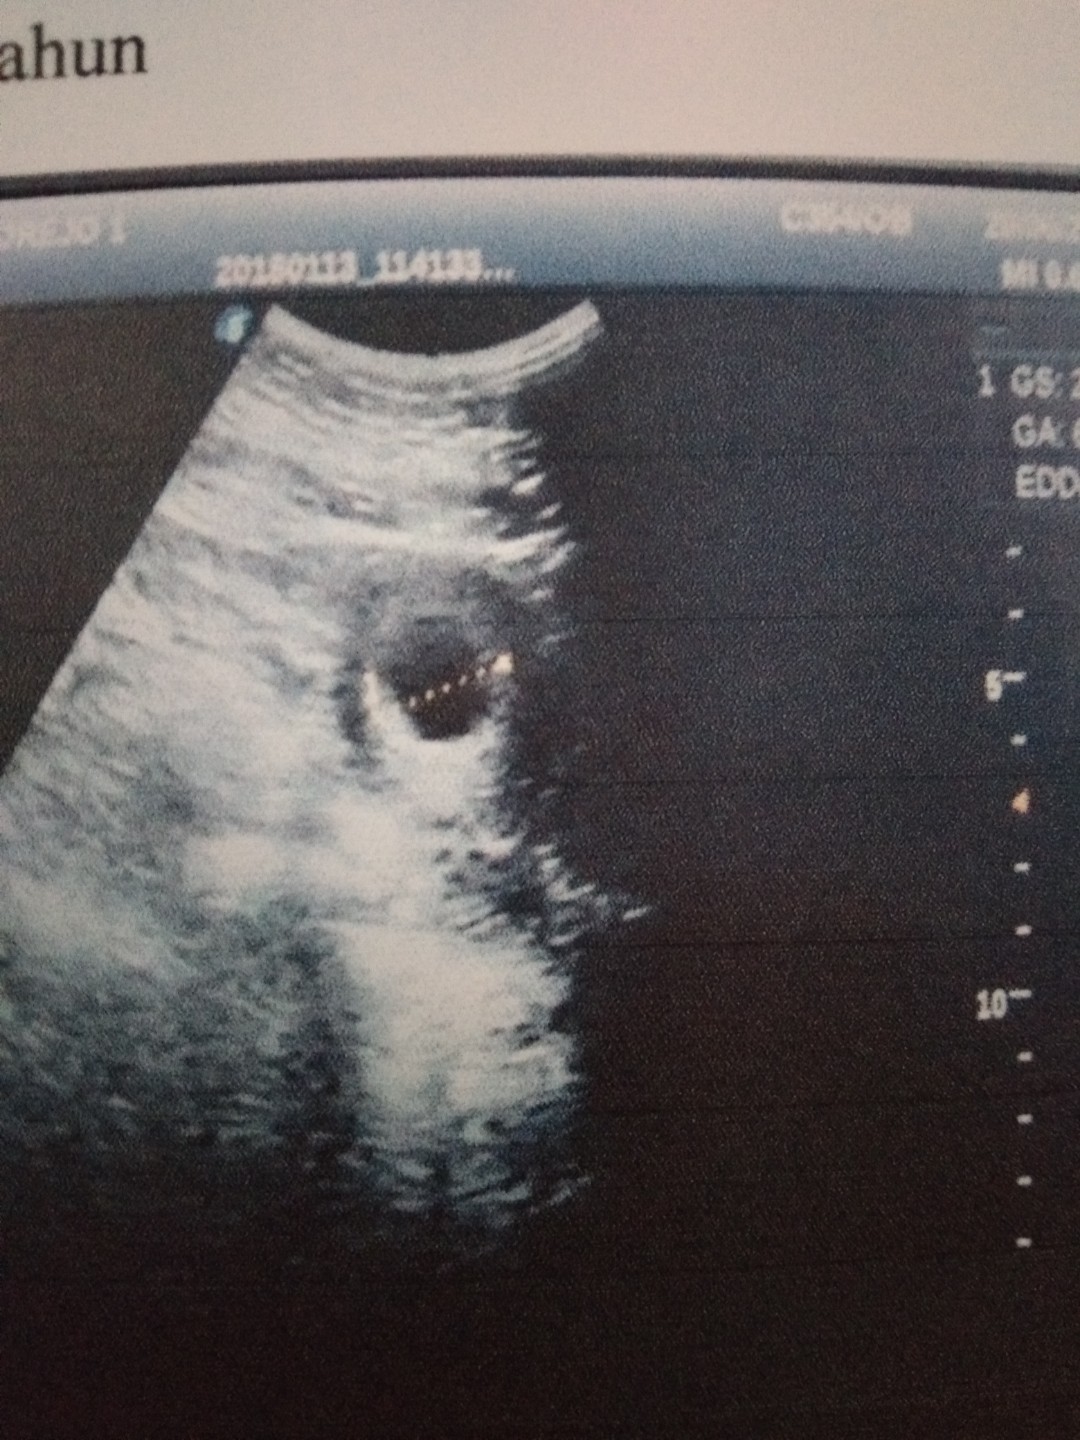

ini punya saya bund uk 6w....skrg udah 17w5d.....positif thinking dl bund, cb usg lagi 2minggu lagi....

Ini saya juga waktu masih 6w bund,, juga masih kantong,,, pas usg ke 2 uk 13w dede nya malah dh gerak"